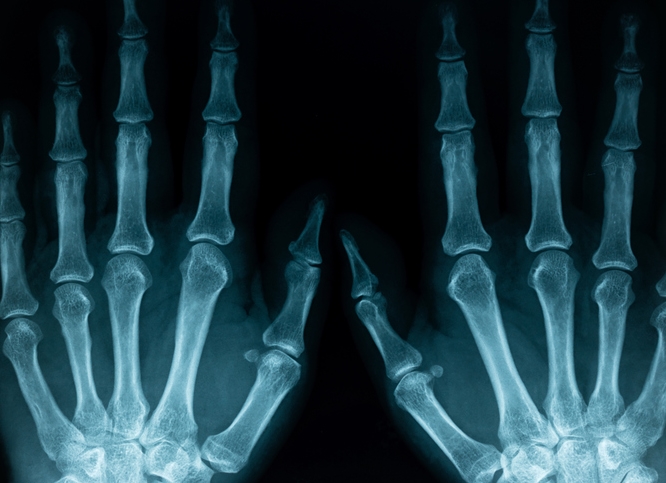

손가락 끝의 통증은 신경 압박, 혈액 순환 장애, 특정 질환 등과 관련이 있을 수 있습니다. 손목터널증후군(정중 신경이 손목에서 압박을 받아 발생하는 증후군)이나 목 디스크(경추 뼈 사이에 있는 디스크가 신경을 압박하는 질환)가 대표적인 원인입니다. 또한, 류마티스 관절염(자가 면역 질환으로 관절에 염증이 생기는 질환)과 같은 염증성 질환도 손가락 끝의 통증을 초래할 수 있습니다.

새끼손가락의 저림은 주로 신경 압박이나 손상으로 인해 발생합니다. 팔꿈치 터널 증후군(팔꿈치 부근의 신경이 압박되어 발생하는 질환)은 새끼손가락과 네 번째 손가락에 저림을 유발할 수 있습니다. 또한, 손목을 과도하게 사용하는 경우, 신경에 압박이 가해져 저림이 발생할 수 있습니다. 이러한 증상이 지속되면, 신경과나 정형외과에서 진단을 받고 적절한 치료를 받는 것이 필요합니다.